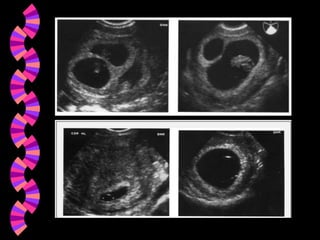

DiagnósticoAmenaza de AbortoAbortoInevitable Aborto en cursoAborto IncompletoAborto CompletoAborto Diferido - Retenido - FrustradoAborto SépticoAborto Recurrente - Aborto HabitualAborto Terapéutico